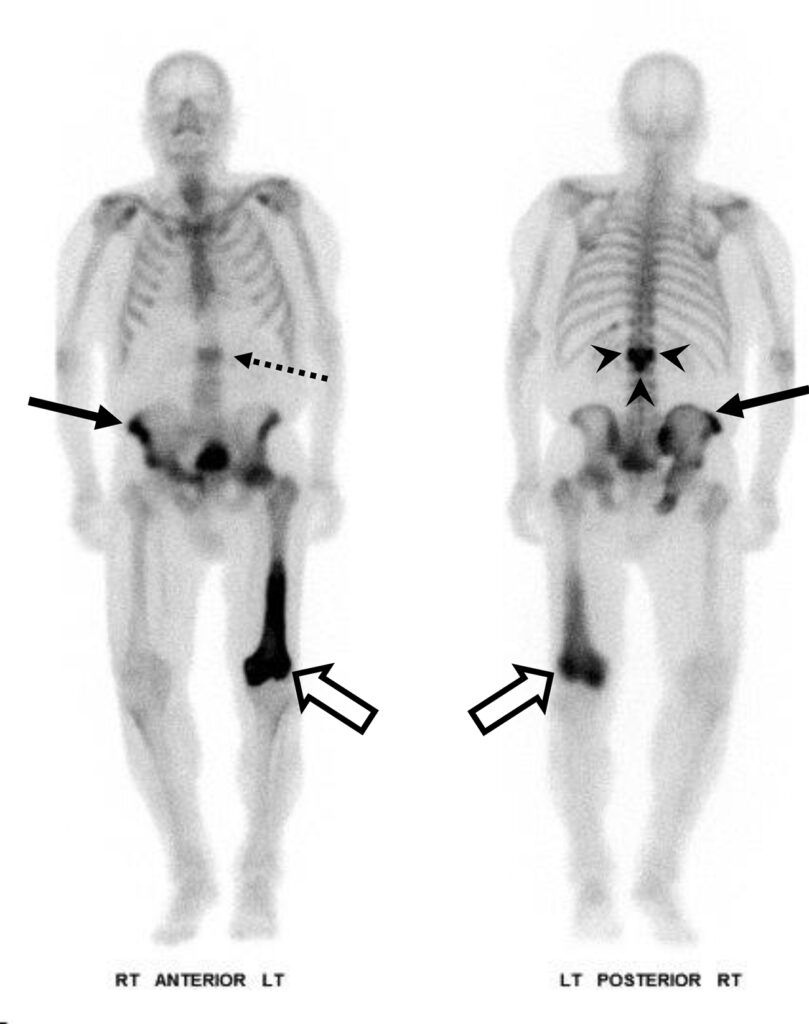

Uomo di 75 anni con tumore alla prostata.

L’immagine planare whole-body in proiezione anteriore della scintigrafia ossea mostra due foci di captazione nella parte inferiore del torace (frecce), sovrapposti alle coste anteriori, inizialmente ritenuti localizzati nelle coste stesse.

L’acquisizione tomografica ibrida risolve definitivamente l’ambiguità spaziale creata dall’immagine planare. Le fette assiali dimostrano che i due focolai di ipercaptazione risiedono nei tessuti molli superficiali sovrastanti le coste, localizzandosi esattamente nel tessuto mammario retroareolare bilaterale.

La captazione simmetrica a livello mammario in un paziente di sesso maschile trattato per neoplasia prostatica è indicativa di ginecomastia indotta da farmaci. L’ipertrofia benigna della ghiandola (che capta il radiotracciante in via extra-ossea) è un ben noto effetto collaterale della terapia di deprivazione androgenica (o della terapia estrogenica).